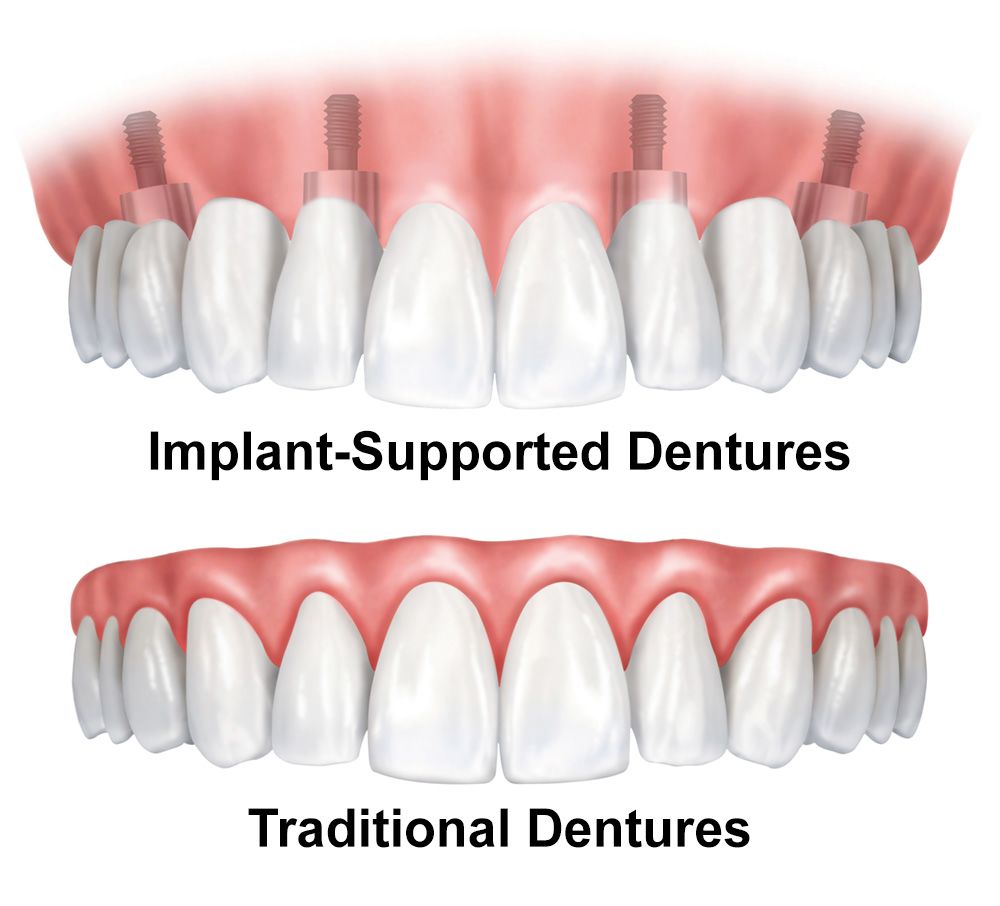

Screw-In Dentures – All About Dental Implants and Dentures

Teeth in a Day

Dentures – Virginia Beach, VA – Dr. Scott Parr – Implant Dentures

What is the average cost for full dental implants – Dental News Network